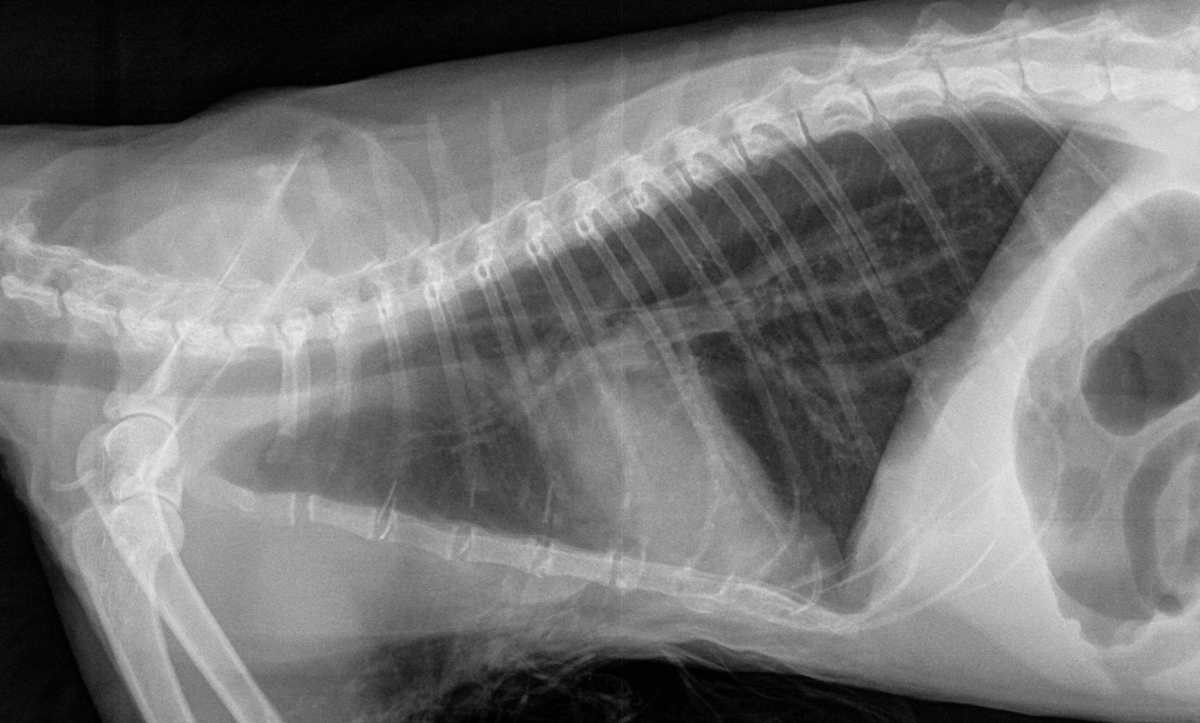

Voici un autre exemple d’hyperinsufflation pulmonaire engendrée par les bronchospasmes et bouchons muqueux qui limitent l’expiration pulmonaire. Cette hyperinsufflation se remarque par la forme de « cloche » du thorax sur la VD. Normalement, le thorax devrait être triangulaire chez le chat. Le diaphragme est aussi aplati sur la latérale. On remarque aussi un patron bronchique léger à modéré, plus facile à voir sur les images magnifiées. Cliquez sur les images pour les voir en haute résolution.